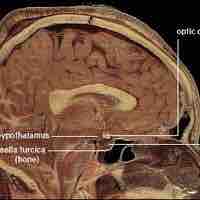

Hypothalamus

The hypothalamus serves as a gateway between the nervous system and endocrine system.